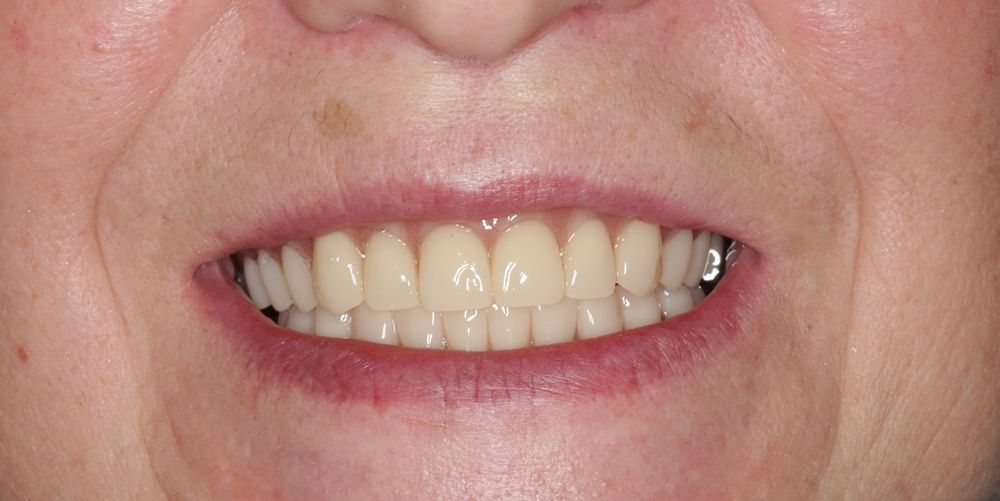

после

до

Имплантация жевательных зубов,

это самая востребованная операция.

Анна Анатольевна Кушнарева

хирург - имплантолог

фото коронок